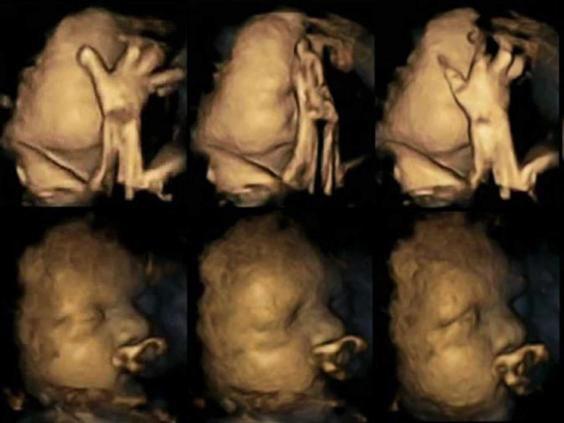

USG 4D ukazujące różnice w rozwoju dzieci matek palących i niepalących

USG 4D ukazujące różnice w rozwoju dzieci matek palących i niepalących © independent.co.uk

Wyniki badań ukazały, że dzieci matek palący w znacznym stopniu rozwijają się wolniej, bowiem wykonują o wiele mniej ruchów ustami i rzadziej dotykają swojej twarzy. Dodatkowo mają większe problemy z kontrolowaniem i koordynacją ruchów.

Lekarze sugerują, że te dzieci, które w łonie matki, zostają wystawione na ekspozycję nikotyny zostają narażone na upośledzenie ośrodkowego układu nerwowego. To powoduje, że rozwijają się wolniej i niestety gorzej. Jeśli znacie palącą ciężarną warto pokazać jej te zdjęcia. Podawajcie dalej!